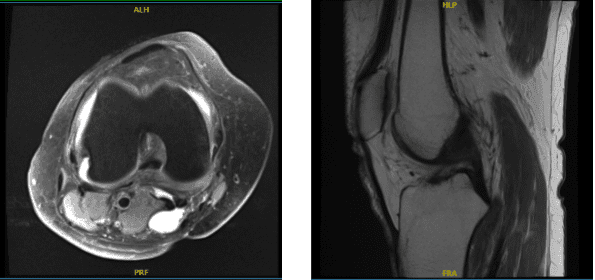

MRI were reviewed and discussed by the doctor, The anterior cruciate, posterior cruciate, medial collateral, and lateral collateral ligaments are intact. A horizontal tear is present at the junction of the body and posterior horn medial meniscus with a 4 mm fragment flipped into the medial joint recess.

A small horizontal tear is present at the junction of the body and anterior horn lateral meniscus. The quadriceps and patellar tendons are intact. The medial and lateral patellofemoral ligaments are unremarkable. A small amount of knee joint fluid is present.

Superficial cartilage irregularity is present in all 3 compartments with almost full-thickness cartilage loss in the medial aspect of the patella that is associated with subchondral bone marrow edema.

Overall, the bone marrow signal is age-appropriate. There is also a small popliteal cyst. The popliteus muscle and tendon are intact and the iliotibial band is within the normal limits and the posterior lateral corner is unremarkable.

Horizontal tear the junction of the body and posterior horn medial meniscus with fragments flipped into the medial joint recess. Horizontal tear at the junction of the body and anterior horn lateral meniscus. It has tricompartmental degenerative changes with cartilage loss most pronounced in the medial aspect of the patella and popliteal cyst.

MRI of knee non-contrast